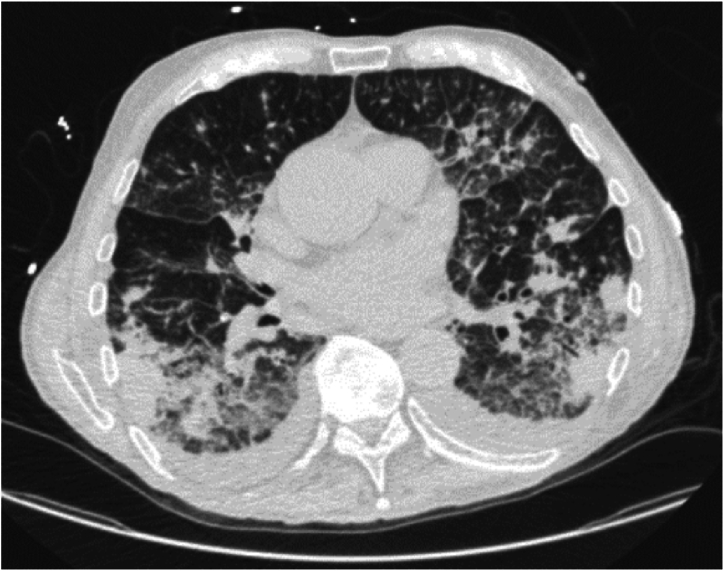

An 89-year-old male with a medical history of non-ischemic cardiomyopathy was initially admitted with acute hypoxic respiratory failure attributed to heart failure exacerbation. Aside from progressive dyspnea, a non-pruritic, non-painful rash and constitutional symptoms were reported. Initial work-up was remarkable for normocytic anemia, lymphopenia, mild hypercalcemia, and elevated inflammatory markers. Despite aggressive diuresis, his respiratory distress worsened requiring up-titration of supplemental oxygen (6–8L/min). Subsequent chest CT showed diffuse, ill-defined areas of consolidation and ground-glass opacities (GGOs) with areas of solid and ground-glass nodularity. Rheumatologic work-up was remarkable for mildly elevated ANA titer of 1:60, and positive anti-centromere antibody of 1.8 AI (normal range 0–0.9 AI). Infectious work-up was negative. Due to high oxygen requirements, tissue sampling was obtained by skin biopsy instead of bronchoscopy. After biopsy testing, prednisone 60 mg was started with posterior clinical and radiographic improvement. Biopsy results revealed cutaneous MZL. Follow-up PET scan showed persistent but improved diffuse GGOs and nodular opacities. Given the clinical presentation, imaging and skin biopsy results, the diagnosis was compatible with EMZL with synchronous pulmonary and skin manifestations. Empiric treatment with Rituximab and steroid taper was planned. At 6-month follow-up, the patient reported clinical and respiratory improvement.